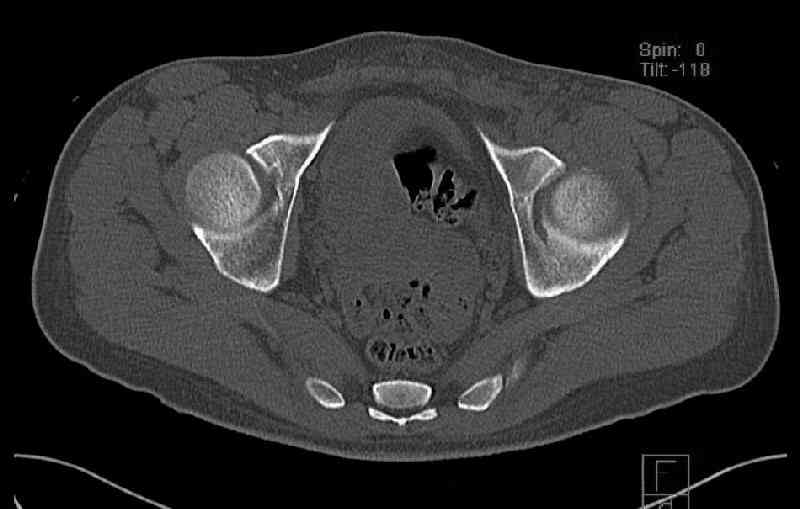

Some more images. Does it help to guess which part of the acetabulum is displaced?

Normal appearing SI joints and a healed posterior column limb... my bet's on caudal segment displacement.

The anterior element of the fracture is so low and the anterior roof arc angle must be at least 60 deg.

The posterior element is so minmally undisplaced. There is good congruence of the joint, and to top it all, 6 weeks have passed. If you consider ORIF now, I don't expect that much improvement could be accomplished. Not to mention the need for extensive approaches with their morbidity.

If you leave him alone now, and if the need arises in the future I believe that a standard THR would be good enough. And this is of course a much simpler procedure than the ORIF currently considered.